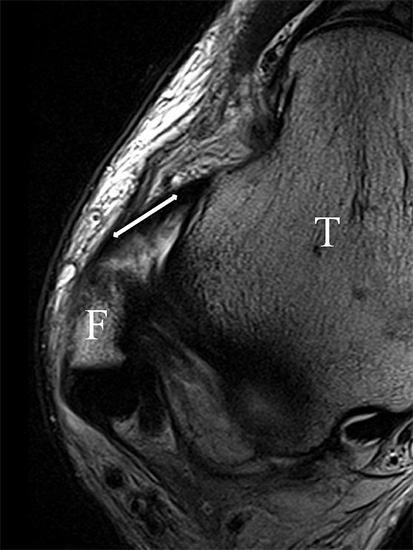

PD fs HR axial. Klare Darstellung eines filigranen, knapp über 1 mm breiten LFTA (Pfeil). Fibula (F).

Abbildung 3

Das LFTA verbindet die antero-inferiore Fibulaspitze mit dem Processus lateralis tali und inseriert hier an einem oder zwei kleinen Tuberkeln 3. Der in Neutralposition horizontale Verlauf erleichtert die kernspintomographische Darstellung in dieser Standardebene. Das LFTA weist durchschnittlich eine Breite von knapp über 2 mm auf 4. Somit sind bei einer Routinedarstellung in 3 mm Schichtdicke Anschnittsphänomene, die die Diagnostik erschweren, regelmäßig anzutreffen. Dementsprechend sind auch die ligamentären Subfaszikel nicht zu differenzieren. In koronarer Darstellung ist dies aufgrund der hohen Auflösung in der Schichtebene jedoch möglich (Abb. 2 a-c), wobei hier wiederum eine Integritätsbeurteilung des Bandes erschwert ist. Unter Verwendung hochauflösender Techniken im Millimeterbereich (Schichtdicke) sind hingegen auch in der axialen Ebene die subfaszikulären Strukturen zu beurteilen (Abb. 3).